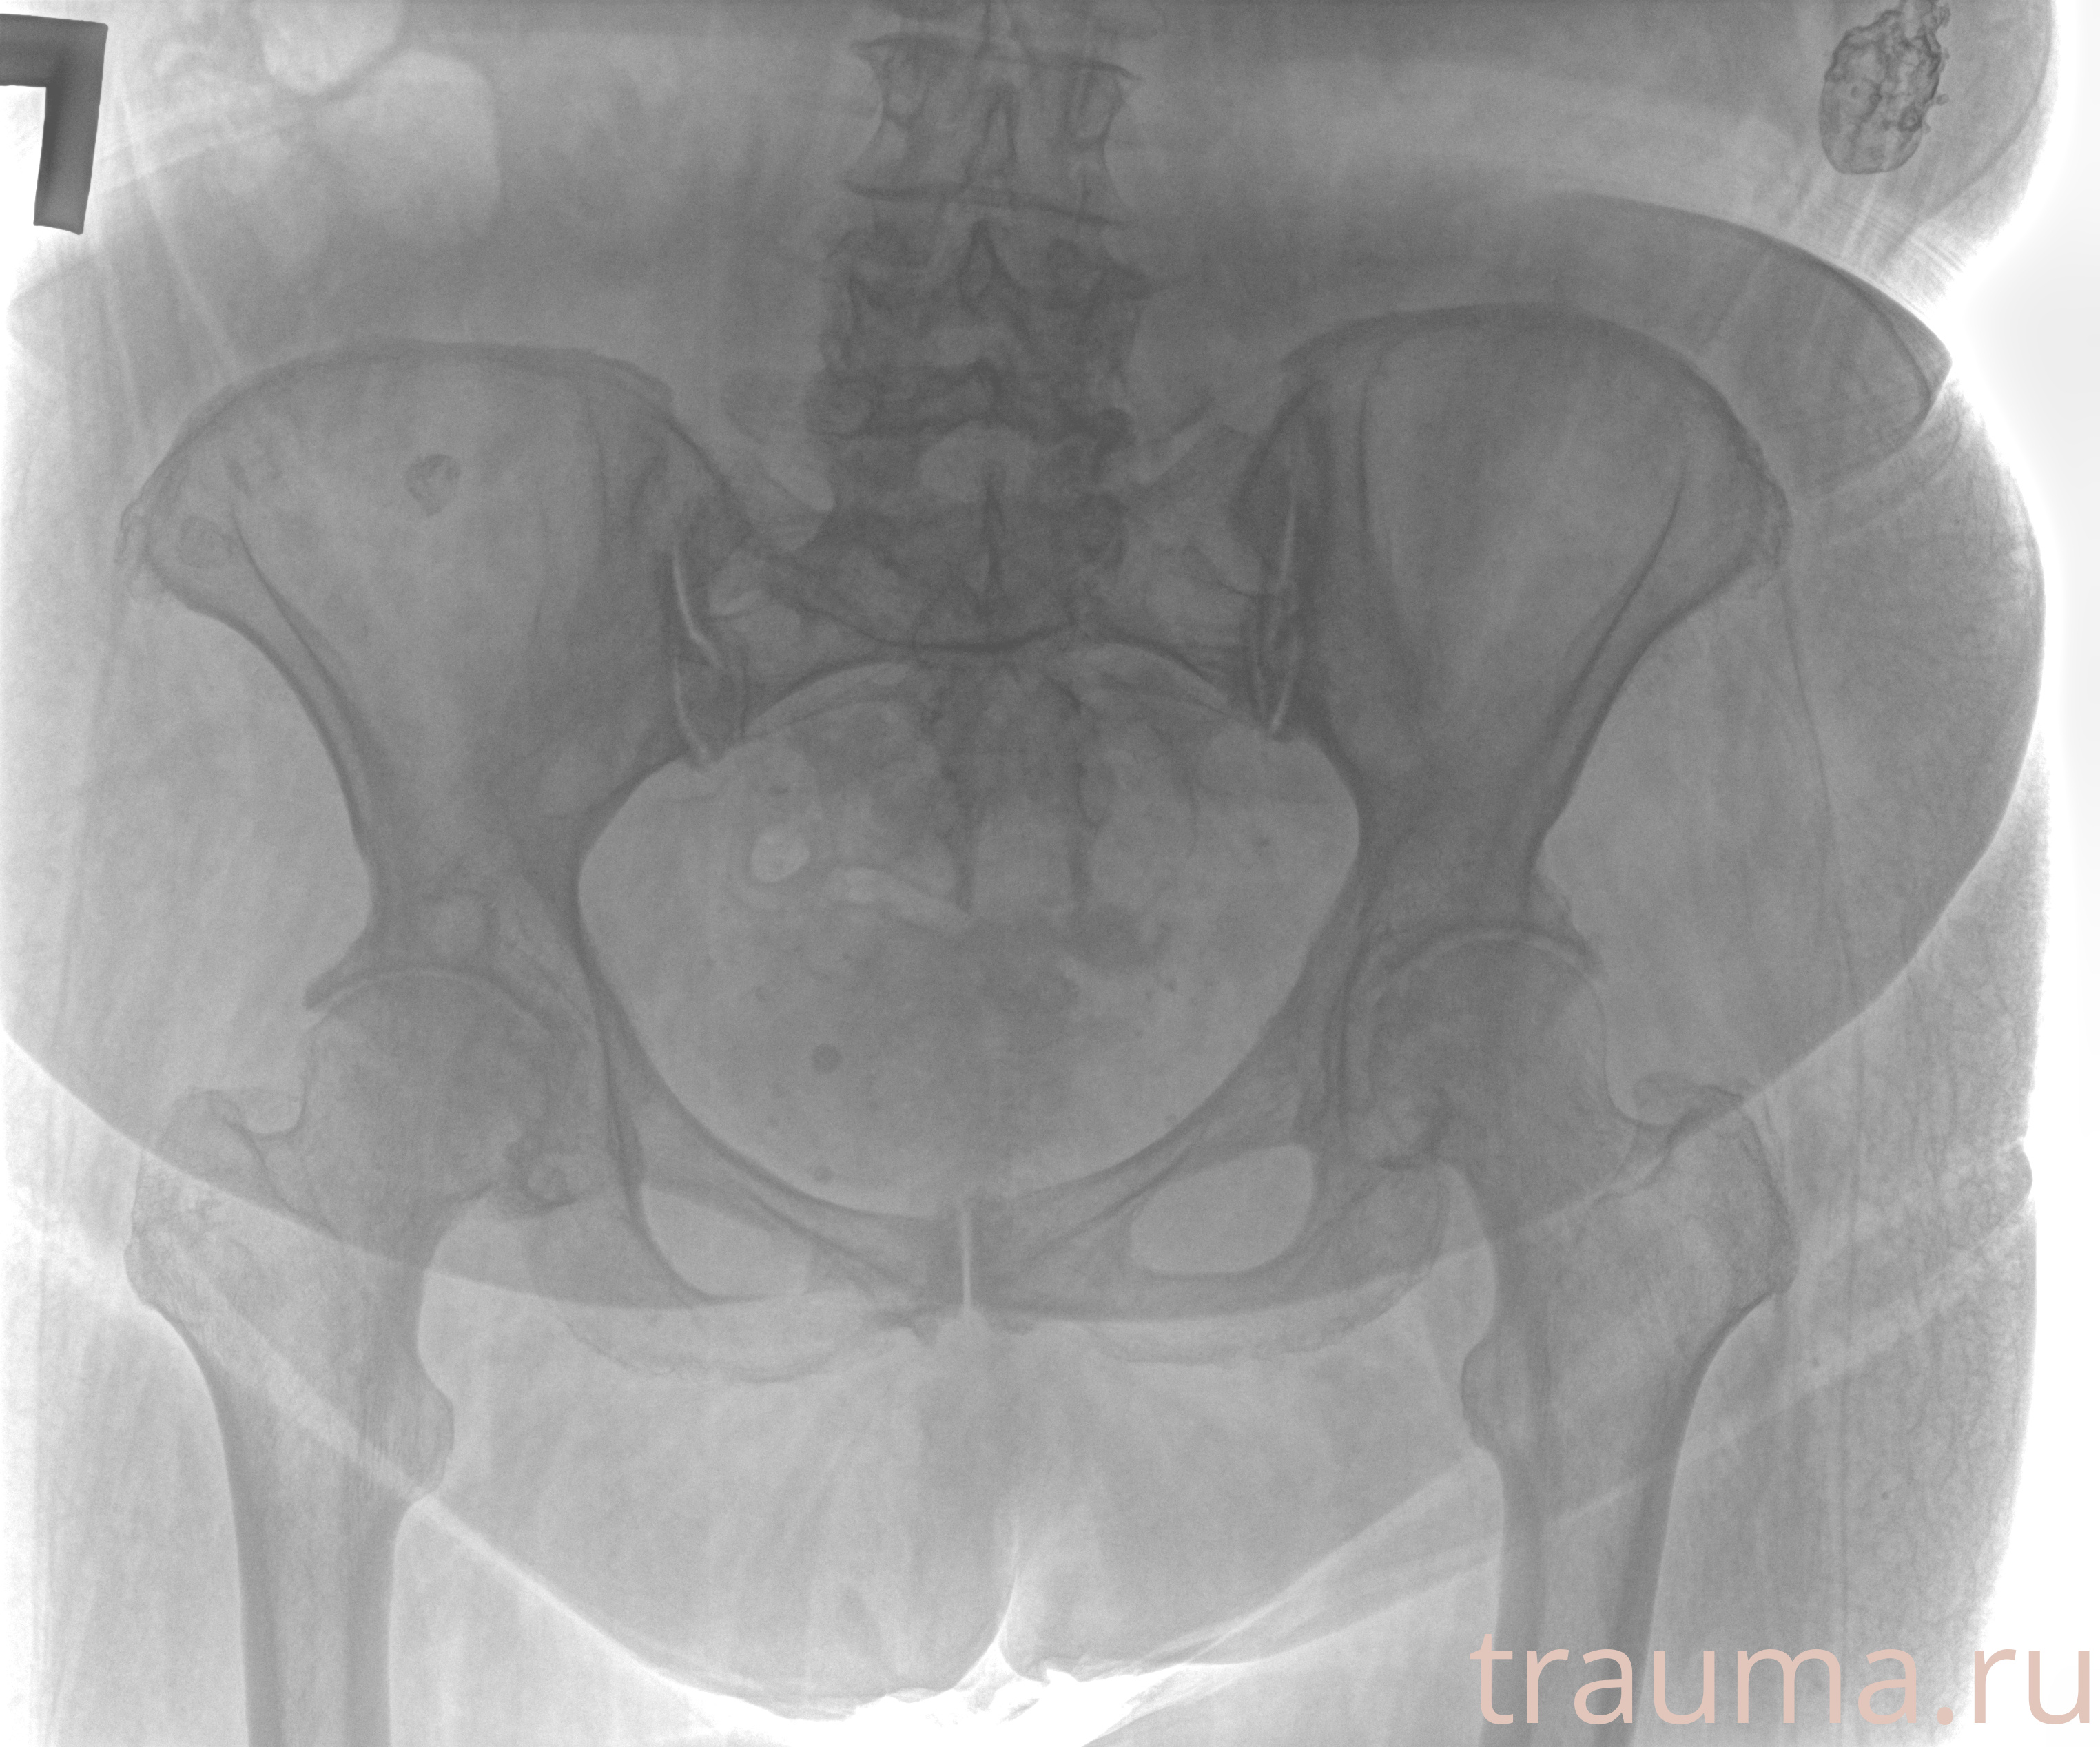

Рентгенограммы

Рентген на дому: по вашему адресу приезжает врач-рентгенолог, травматолог-ортопед с мобильным рентгеновским аппаратом, проводит диагностику травмы или заболевания, делает необходимые рентгенограммы, дает рекомендации по дальнейшему лечению. Получить качественные снимки в домашних условиях возможно благодаря уникальной методике, разработанной МосРентген Центром для института  Склифосовского